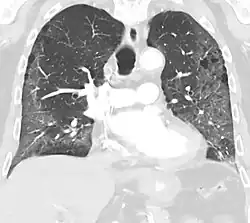

CT showing diffuse ground-glass opacities in periphery of both lungs in patient with COVID-19.

Ground-glass opacity is among the most common imaging findings in patients with confirmed COVID-19.[16][17] One systematic review found that among patients with COVID-19 and abnormal lung findings on CT, greater than 80% had GGOs, with greater than 50% having mixed GGOs and consolidation.[16] GGOs with mixed consolidation has most often been found in elderly populations.[18]

Several studies have described a pattern among initial, intermediate, and hospital discharge imaging findings in the disease course of COVID-19. Most commonly, initial CT imaging reveals bilateral GGOs at the periphery of the lungs. During initial stages, this is most often found in the lower lobes, although involvement of the upper lobes and right middle lobe has also been reported early in the disease course.[16][18] This is in contrast to the two similar coronaviruses, SARS and MERS, which more commonly involve only one lung on initial imaging.[19][20] As the COVID-19 infection progresses, GGOs typically become more diffuse and often progress to consolidation.[11][18] This is sometimes accompanied by the development of a crazy paving pattern and interlobular septal thickening.[18] In many cases the most severe pulmonary CT abnormalities occurred within 2 weeks after symptoms began.[17] At this point, many individuals begin showing resolution of consolidation and GGOs as symptoms improve. However, some patients have worsening symptoms and imaging findings, with further increase in septal thickening, GGOs, and consolidation. These patients may develop lung "white-out" with progression to acute respiratory distress syndrome (ARDS) requiring treatment escalation.[17][21]